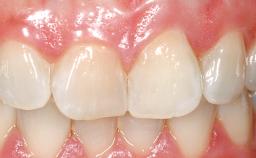

A 33-year-old female patient presented with an upper left central incisor that required extraction after a failed endodontic therapy. The tooth had been traumatized when the patient was a teenager and had undergone several endodontic treatments, including two apicectomy procedures. The patient was in good health and did not smoke. Clinical examination showed that the patient had a high lip line. In full smile, the gingival margins of the upper teeth were visible to the first molars. The gingival margins of central incisors 11 and 21 were only just showing. Examination of tooth 21 confirmed that the tooth was mobile and had hypererupted by 1 mm.